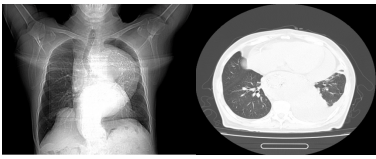

▲一位尚未透析的终末期肾脏病患者

也就是我们常说的“围透析期”,通常发生在刚开始透析,或者透析不充分的患者身上透析不充分,我们图中第二例患者就是一位未及时开始透析的终末期透析患者。如果透析次数不够、时间不足,毒素清除得不够理想,依然会持续刺激心包。